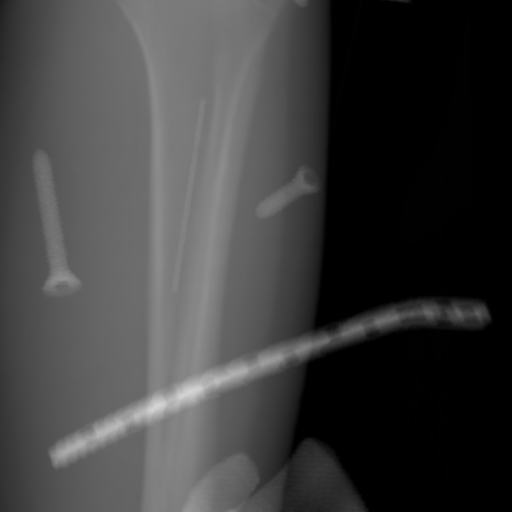

5.4 Real Knee Data with Metal Implants

Refer to caption

Figure 13: Three examples of synthetic perspective projection images for training, intensity window: [0, 4]. The appearance (e.g., image contrast and metal image resolution) of such DRR training images is different from that of real projection images in Fig. 14.

The complementary view setting for learning perspective deformation is also evaluated on real CBCT projection data. In this evaluation, real CBCT projection data from a dataset of knees with metal implants is used for testing, while DRRs created from volumetric CT datasets with inserted metals is used for training. Three exemplary DRR perspective projection images for training are displayed in Fig. 13, in which synthetic metal implants are inserted [34]. The appearance, e.g., image contrast and metal image resolution, of such DRR training images is different from that of real projection images in Fig. 14. In Fig. 14, the results for three knees, with and without metal implants, are displayed. The first and second rows are the 0superscript00^{\circ} and 180superscript180180^{\circ} perspective projections, respectively, rebinned to the virtual detector with geometric calibration based on their respective principal points and projections of the world origin. The third row displays their difference images, where the magnitude of deviation increases from the center towards the outside like it does in DRRs with an ideal scan trajectory (e.g., Fig. 6(e)), although real projection data suffer from various physical effects like beam hardening and Poisson noise. The fourth row displays the RGB stacks of 0superscript00^{\circ} and 180superscript180180^{\circ} perspective projection images. The magenta and green regions indicate structures with considerable perspective deformation, for example, the knee patella in Fig. 5.4, the top parts of the two metals in Fig. 5.4, and the bottom two screws in Fig. 5.4. The fifth row displays reference images, which are orthogonal projections of iterative reconstruction volumes from measured CBCT projection data. In the reference images, a total of five landmarks are selected, with the positions being marked by the green dots: In Fig. 5.4, two positions at the edges of the knee patella are marked; In Fig. 14(e) and Fig. 14(f), one position at the left edge of the fibula is marked for each image. In addition, a rectangular frame for the two metals is marked by the green dashed lines, while its width and height are indicated by the green solid lines, which are 29.71 mm and 111.99 mm, respectively. In Fig. 14(f), the centerlines of the bottom two screws are sketched by the green lines, which have the lengths of 17.14 mm (middle screw) and 19.38 mm (bottom screw). The corresponding rectangular frame for the two metals and the screw centerlines in the perspective projection images are marked as well, but in red color. In Fig. 14(a), the width and height of the metals are 32.56 mm and 109.85 mm, which have deviations of 2.84 mm and -1.95 mm to the reference ones, respectively. In Fig. 14(b), the centerline lengths are 18.91 mm and 19.54 mm, which have deviations of 1.77 mm and 0.16 mm, respectively. Although the bottom screw has little length deviation to the reference, the orientations of both screws are obviously deviated. The sixth row shows the results of Pix2pixGAN using 0superscript00^{\circ} and 180superscript180180^{\circ} polar inputs. For all of the landmarks, the green reference dots are all located accurately in the Pix2pixGAN images. The rectangular reference frame also accurately covers the metals in Fig. 14(g). In Fig. 14(h), although the two red centerlines do not exactly overlap with the green one, they are very close in lengths and orientations. Please zoom in for better visualization.